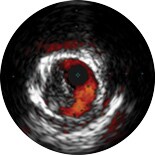

Intravascular ultrasound allows physicians to visualize blood vessels from the inside out. Cross-sectional images help assess presence and extent of disease, plaque geometry and morphology, guide wire position during lesion crossing, and stent position post-treatment. The imaging transducer emits high-frequency sound waves that echo off vessel walls and are sent back to the system in varying intensities depending on the tissue. System electronics process the signal to display the cross-sectional image.

IVUS can help clarify the degree and type of stenosis (i.e, minimum lumen area, plaque burden, and calcium). While IVUS can help characterize plaque rupture, thrombus, and dissection, it can also help identify calcified lesions that show up as bright areas with acoustic shadowing and/or reverberations in IVUS images

• Normal-looking vessel with IVUS

Normal-looking vessel with IVUS

• Plaque with calcium

Plaque with calcium

• Stent with complete apposition

Stent with complete apposition

• Stent with malapposition

Stent with malapposition

• Concentric Mixed Plaque

Concentric Mixed Plaque